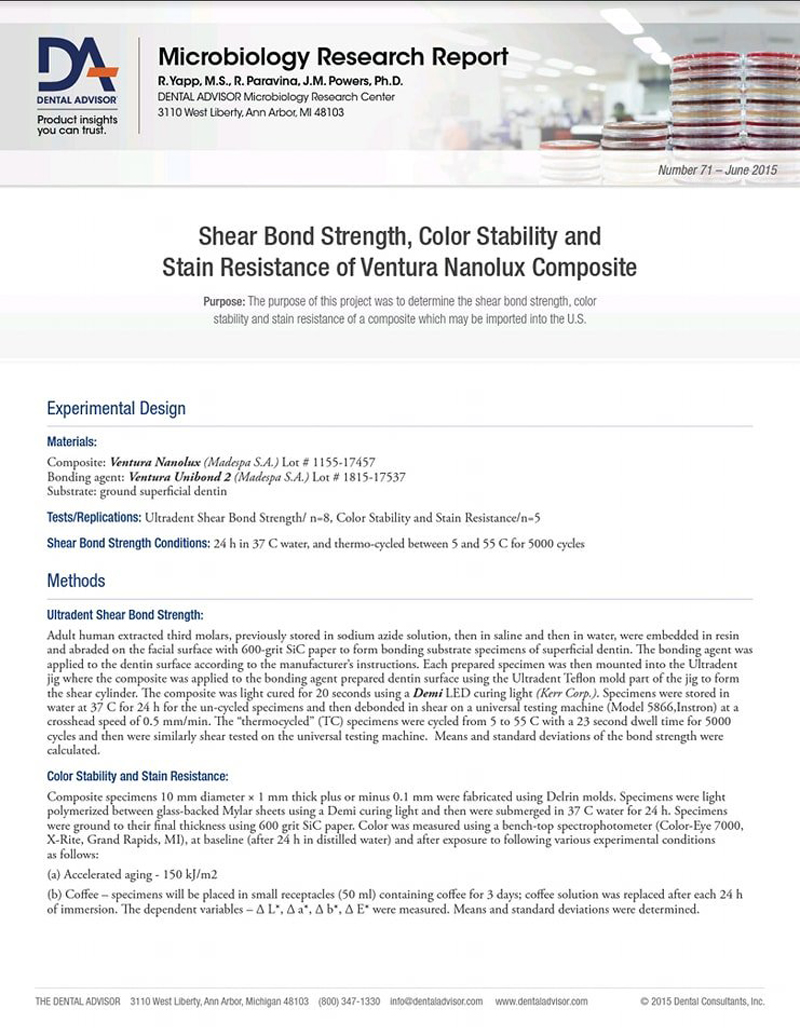

RAPORT BADAWCZY DAMICROBIOLOGY - VENTURA NANOLUX

Napisała Katarzyna SiekluckaVERNTURA NANOLUX to uniwersalny kompozyt, który reprezentuje estetykę, zachowanie połysku , odporność na przebarwienia i wysoką wytrzymałość. Siła wiązania, ścierania, stabilność kolorów i odporność na plamę kompozytową.

Zdjęcie 1

-

Zdjęcie 2